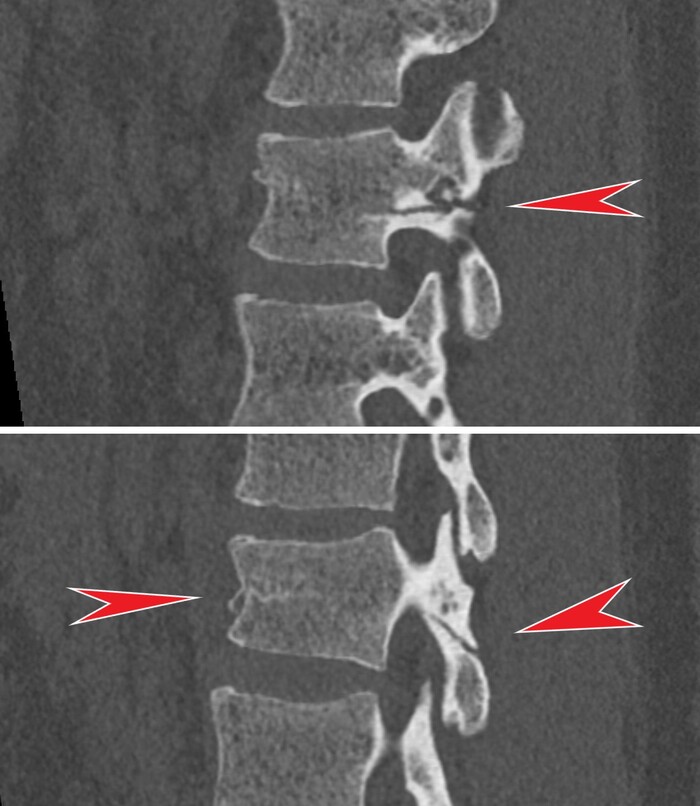

На 3й день после травмы из комы так и не вышла, посему сделали МРТ, на котором обнаружились участки повышенного сигнала на Т2-взвешенных изображениях на границе серого и белого вещества фронтально и темпорально справа, а также в область правого таламуса и в заднем отделе мозолистого тела т.н. сплениуме:

которые визуализировались и на FLAIR:

Очаги показывали также ограниченную диффузию на DWI-изображениях: